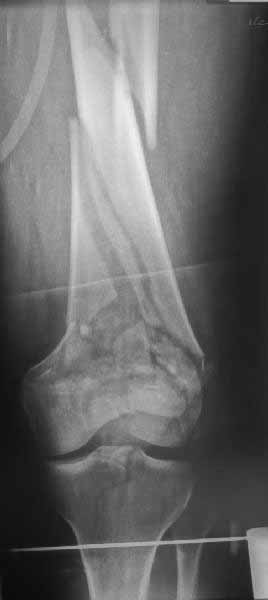

Однако в случае, представленном Константином Никитиным, не может быть применён ни ретроградный ни антеградный остеосинтез. Причина - нереально выполнить вышеуказанные необходимые требования, касающиеся дистальных блокирующих винтов. Из-за низкого перелома латерального мыщелка (перелом Hoffa) невозможно через него провести хотя бы 2 блокирующих винта, поскольку линия перелома мыщелка расположена либо на уровне верхушки межмыщелковой ямки либо незначительно проксимальнее. Поэтому авторам, с моей точки зрения, необходимо прислушаться к рекомендациям Джолдаса.

VLaD! Согласен...но не во всем. Действительно, и Вы сами это определили, гвоздь является "золотым стандартом"для ДИАФИЗАРНЫХ и метадиафизарных переломов длинных трубчатых костей ( а вот плечо???). Но в данном случае мы с Вами имеем дело с внутрисуставным повреждением и даже после успешной его репозиции и адекватной фиксации диафизарным оно от этого не стало. Зачем нужно вносить дополнительный риск вторичного смещения его внутрисуставного компонента, ведь адекватности фиксации (создание абсолютной стабильности)этой области при помощи интерлокинга и закрыто проведенных изолированных винтов добиться сложнее, нежели комплексом винты+пластина с винтами, изготовленная для переломов именно этой локализации?